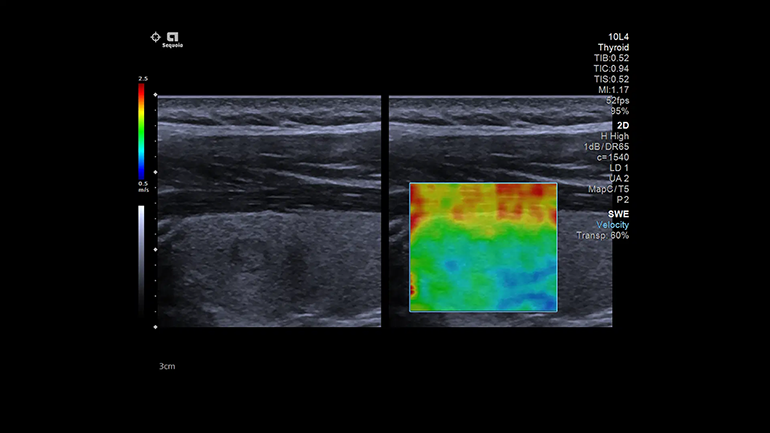

Технология 2D SWE

В режиме 2D SWE высокая плотность оцифровки ЭХО-сигнала обеспечивает высокое пространственное разрешение и отличные результаты по значениям жесткости для повышения качества визуализации очаговых поражений и диффузно-неоднородных тканей. Измерения можно выполнять в заданных локациях для определения жесткости ткани, используя значения м/с или кПа.

Графические изображения результатов. Карты качества

Карты качества позволяет немедленно оценить качество сдвиговых волн и повысить достоверность диагностики.